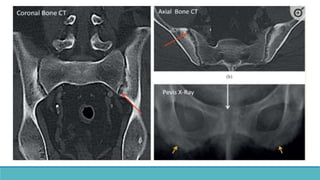

• Cortical bone erosion – Phalanges

•Most sensitive site : Radial aspects of

middle phalanges of index and middle

fingers.

• Tufts of distal phalanges.

•Acrosteolysis – distal phalanges, Outer

clavicle, pubic symphysis, sacroiliac joints,

proximal medial cortex of tibia, proximal

humeral shaft, ribs and femur.

• Cortical boneerosion – Phalanges •Most sensitive site : Radial aspects of middle phalanges of index and middle fingers. • Tufts of distal phalanges. •Acrosteolysis – distal phalanges, Outer clavicle, pubic symphysis, sacroiliac joints, proximal medial cortex of tibia, proximal humeral shaft, ribs and femur.